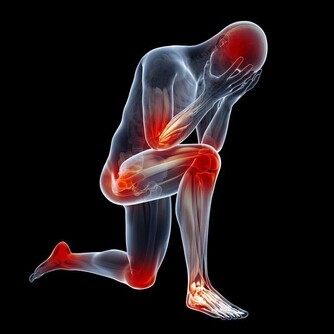

可以治療身體的酸痛、便秘、感冒、頭痛、

可消除疲勞、增進食慾、可以化食、解酒,

提高思考反應的靈活度、腳部酸痛、